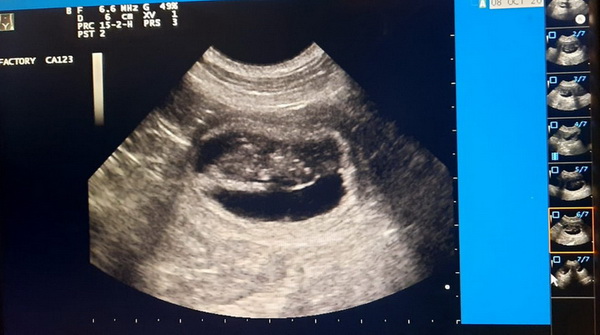

Op 1 en 2 januari 2021 was het tijd voor de pups om het nest te verlaten. Op 7 november was het zover. Er werden een aantal pups geboren. Op 8 november nog 1. Daarna stopte de weeën. De laatste pup werd levend en wel geboren via een keizersnede. Wat waren wij gelukkig met ons 5tal. Twee dagen na de keizersnede begonnen de problemen. De wond van Kestra ging ontsteken. Helaas een AB-kuur met alle ellende die erop volgde. Maar goed wij hadden geen keuze. Toen ze weer op krabbelde kregen wij weer een klap te verduren. Wij moesten ons lieve meisje paars in laten slapen op 12 november 2020. Omdat ze geen eigenaar heeft gekend hebben wij haar Sterre genoemd. Alle stamboom namen beginnen daarom met Star... Sterre 07-11-2020 tot 12-11-2020 In mijn handen geboren en in mijn handen gestorven, mijn hart zul je nooit verlaten. 8 oktober 2020 Kestra is drachtig. Onze wachtlijst is vol. 4 oktober 2020 Nog even geduld en wij weten of wij pups verwachten. 9 september, vandaag is Kestra gedekt door Smoke. 26 augustus, vandaag is Kestra loops geworden.